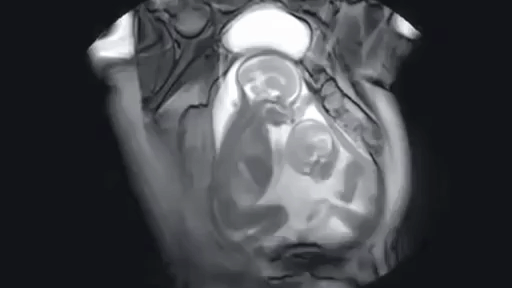

9. МРТ жінки, яка вагітна двійнею